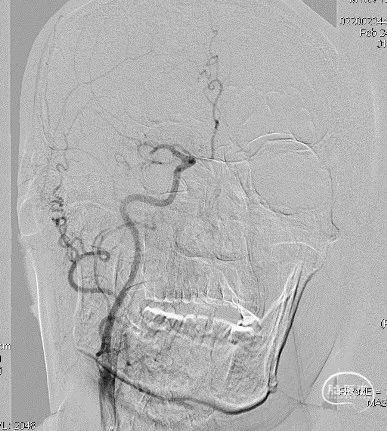

局麻,右股动脉入路置8F短鞘,导管导丝技术将8F MPA置于右C1末端,造影确认右M1急性闭塞,侧支代偿差。

以Transend-14导丝 + Headway21导管到达M1中段,Sofia Plus顺畅到位(M1中段),ADATP技术抽吸取栓,一次成功取通,前向血流TICI 3级,无栓子逃逸及原位狭窄,穿刺至开通时间仅用时9min。

DSA造影见右侧大脑中动脉M1中段以远闭塞,ACA向MCA区域仅少量代偿。Sofia Plus在Headway21导管及Transend导丝引导下,很顺畅通过虹吸段等部位,到达M1中段。

采用ADAPT技术,血流快速复通;最右图为Sofia Plus导管前端及取出血栓。